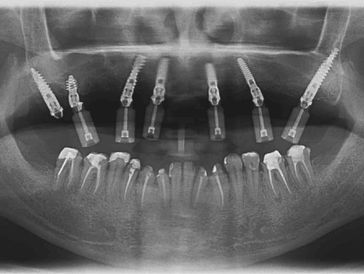

Backed by 45+ years of combined experience, trusted for the toughest cases, including zygomatic and pterygoid implants